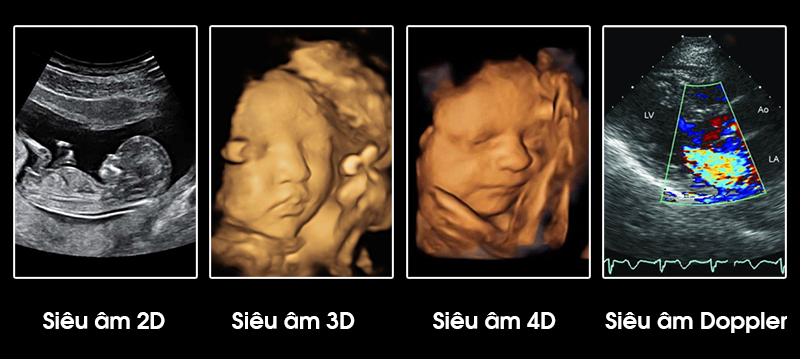

Có nhiều loại siêu âm thai khác nhau, dựa trên mục đích và phạm vi của cuộc siêu âm. Dưới đây là một số loại phổ biến:

Siêu Âm 2D (2 chiều): Siêu âm 2D tạo ra hình ảnh phẳng và đơn sắc của thai nhi. Nó được sử dụng để theo dõi sự phát triển cơ bản và xác định giới tính thai nhi.

Siêu Âm 2D (2 chiều): Siêu âm 2D tạo ra hình ảnh phẳng và đơn sắc của thai nhi. Nó được sử dụng để theo dõi sự phát triển cơ bản và xác định giới tính thai nhi.

Siêu Âm 3D (3 chiều): Siêu âm 3D tạo ra hình ảnh thai nhi trong ba chiều, cho phép xem rõ hơn các chi tiết của khuôn mặt và cơ thể thai nhi. Nó mang lại trải nghiệm hình ảnh trực quan hơn cho bố mẹ.

Siêu Âm 3D (3 chiều): Siêu âm 3D tạo ra hình ảnh thai nhi trong ba chiều, cho phép xem rõ hơn các chi tiết của khuôn mặt và cơ thể thai nhi. Nó mang lại trải nghiệm hình ảnh trực quan hơn cho bố mẹ.

Các loại siêu âm thai nhi

Siêu Âm 4D (4 chiều): Siêu âm 4D là một biến thể của siêu âm 3D với khả năng theo dõi chuyển động thời gian thực của thai nhi. Bố mẹ có thể xem thai nhi cười, hoặc đặc biệt là các biểu cảm trên khuôn mặt của con.

Siêu Âm 4D (4 chiều): Siêu âm 4D là một biến thể của siêu âm 3D với khả năng theo dõi chuyển động thời gian thực của thai nhi. Bố mẹ có thể xem thai nhi cười, hoặc đặc biệt là các biểu cảm trên khuôn mặt của con.

Siêu Âm Doppler: Siêu âm Doppler sử dụng sóng âm để đo tốc độ dòng máu trong mạch máu của thai nhi và tử cung của mẹ. Nó được sử dụng để đánh giá tình trạng của cả thai nhi và tình trạng của mạch máu của mẹ.

Siêu Âm Doppler: Siêu âm Doppler sử dụng sóng âm để đo tốc độ dòng máu trong mạch máu của thai nhi và tử cung của mẹ. Nó được sử dụng để đánh giá tình trạng của cả thai nhi và tình trạng của mạch máu của mẹ.